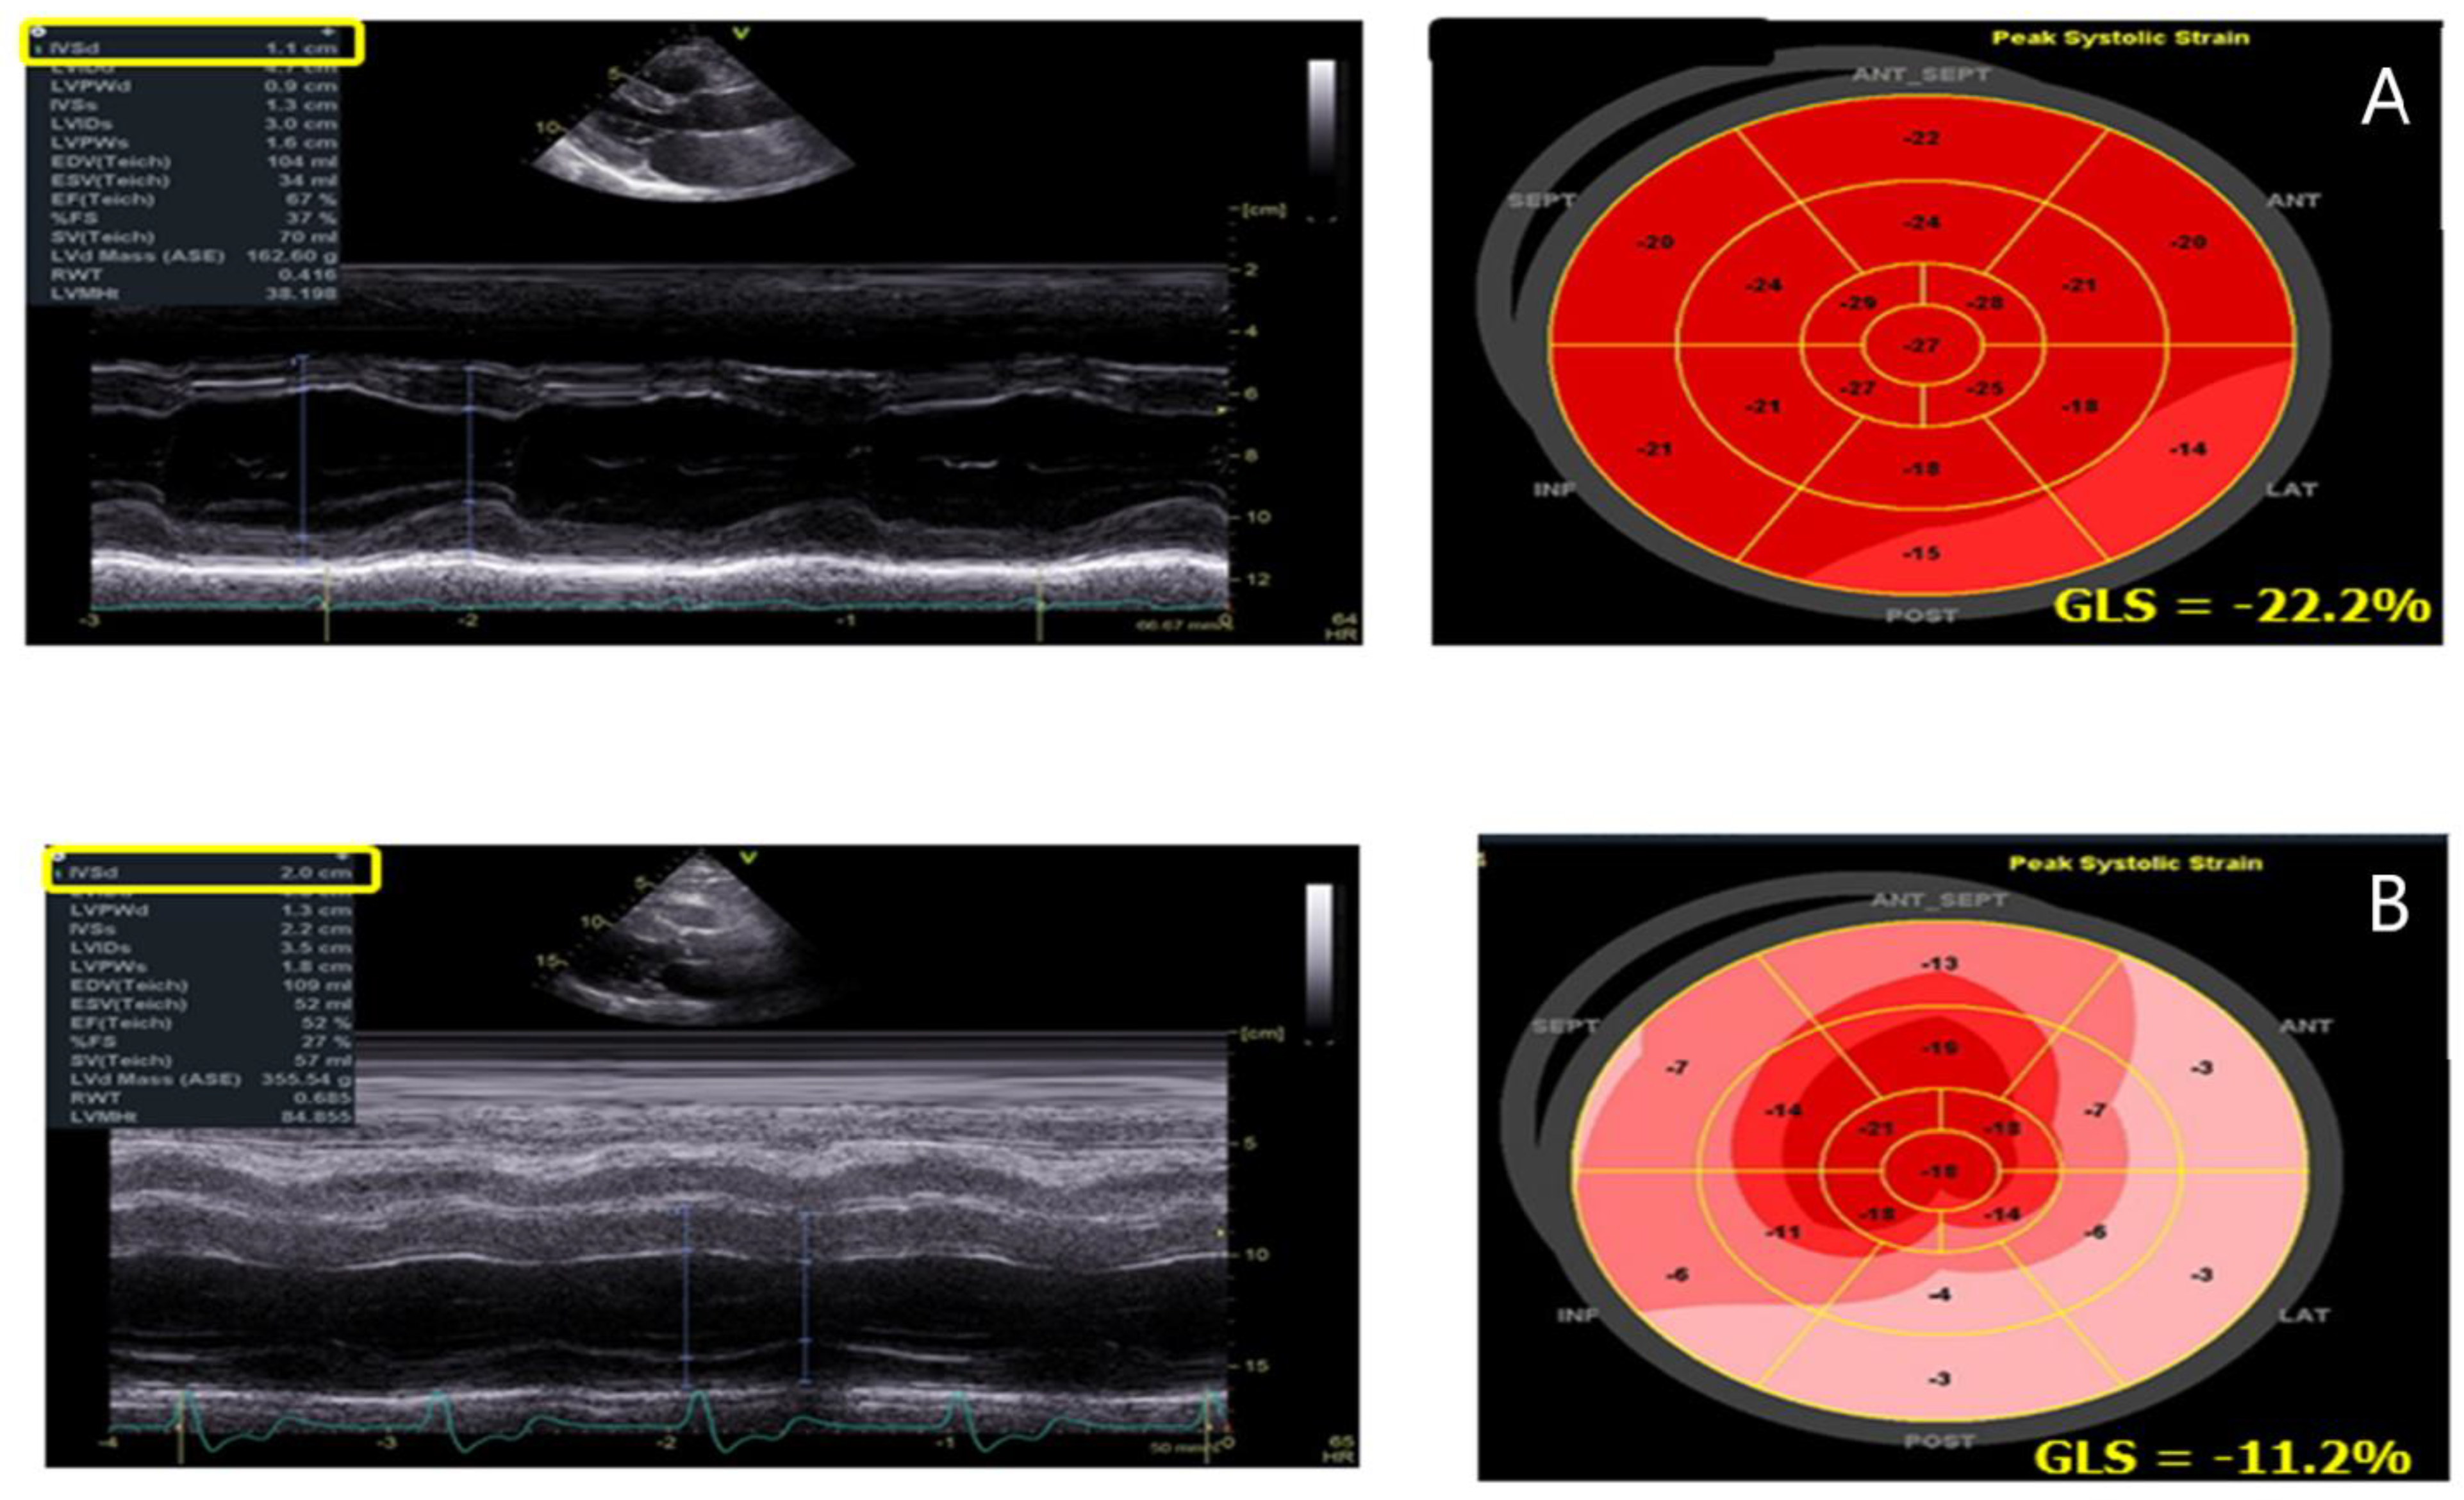

- D’Andrea, A.; Radmilovic, J.; Ballo, P.; Mele, D.; Agricola, E.; Cameli, M.; Rossi, A.; Esposito, R.; Novo, G.; Mondillo, S.; et al. Left ventricular hypertrophy or storage disease? the incremental value of speckle tracking strain bull’s-eye. Echocardiography 2017, 34, 746–759. [Google Scholar] [CrossRef] [PubMed]

- Esposito, R.; Galderisi, M.; Santoro, C.; Imbriaco, M.; Riccio, E.; Maria Pellegrino, A.; Sorrentino, R.; Lembo, M.; Citro, R.; Angela Losi, M.; et al. Prominent longitudinal strain reduction of left ventricular basal segments in treatment-naïve Anderson-Fabry disease patients. Eur. Heart J. Cardiovasc. Imaging 2019, 20, 438–445. [Google Scholar] [CrossRef] [PubMed]

- Liu, D.; Hu, K.; Nordbeck, P.; Ertl, G.; Störk, S.; Weidemann, F. Longitudinal strain bull’s eye plot patterns in patients with cardiomyopathy and concentric left ventricular hypertrophy. Eur. J. Med. Res. 2016, 10, 21. [Google Scholar] [CrossRef]

| GLS | -Reduction in LV GLS with a prevalent involvement of the infero-lateral wall of the LV | -Correlates with LGE at CMR |